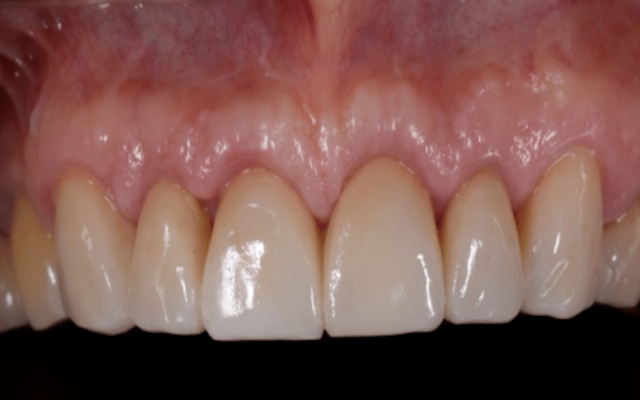

Following crown lengthening, the gum has been repositioned to expose enough tooth structure for restoration with crowns.

The teeth have now been restored with long lasting crowns.